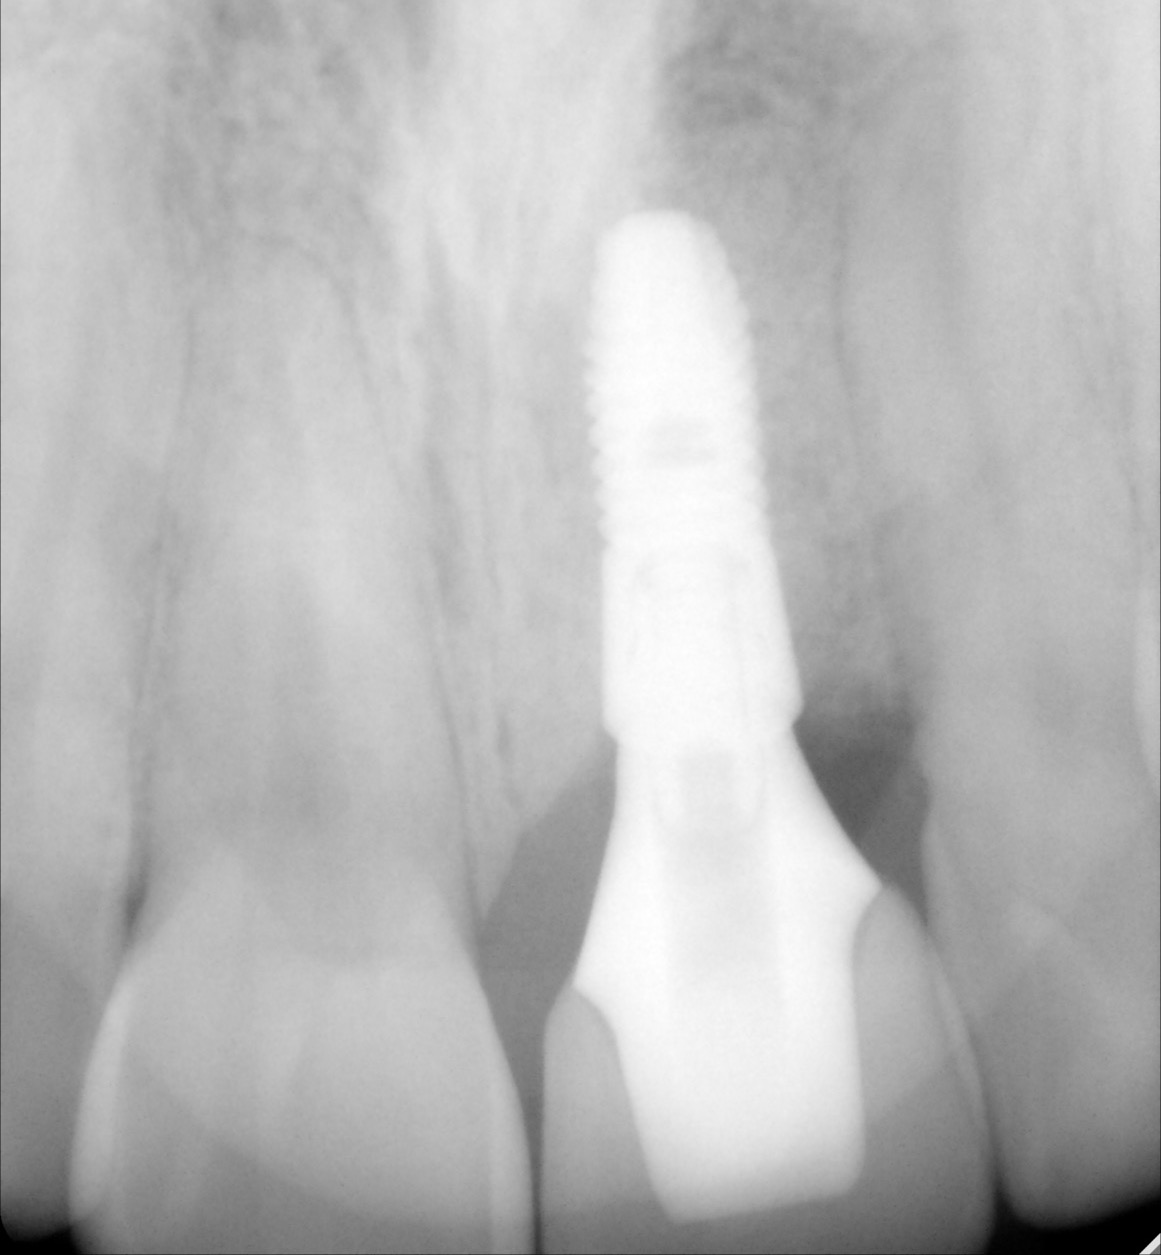

A dental implant is a titanium post that serves as a replacement for the root of a missing tooth. The implant is surgically inserted into the jawbone, where it is fused with the bone as the latter heals over time in a process called osseointegration. Once integrated, the implant becomes a sturdy foundation for one or more artificial teeth.

- Implant post: The titanium screw that is placed into the jawbone.

- Abutment: The connector piece that attaches the implant post to the restoration.

Following the surgery, the implant undergoes a process called osseointegration, wherein it is fused with the bone as the latter heals over a period of three to six months. Some patients may have a temporary tooth or other prosthetic attached during the same appointment, while others may require multiple visits to ensure optimal healing and placement.